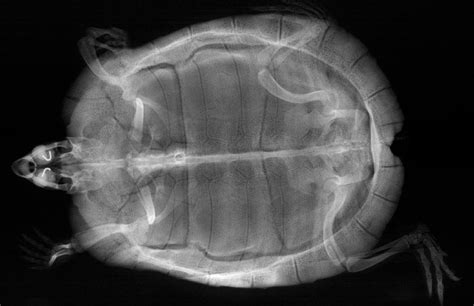

Alright, so we’ve established why turtle X-rays are super important, but let’s get down to the nitty-gritty: what exactly can these incredible images show us ? When your turtle undergoes an X-ray, it’s like getting a secret blueprint of their internal architecture, revealing a wealth of information crucial for accurate diagnosis. It’s honestly amazing what a skilled reptile veterinarian can deduce from a few well-positioned radiographs. Let’s break down some of the most common and critical conditions that these powerful turtle X-ray diagnostics can unveil, giving vets the information they need to formulate the best possible treatment plan for your little (or not-so-little) shelled buddy.

One of the most frequent findings on a turtle X-ray is related to bone health , particularly conditions like Metabolic Bone Disease (MBD) . This is a very common issue in captive reptiles, often due to improper diet (lack of calcium or vitamin D3) and inadequate UV light exposure. On an X-ray, MBD can manifest as generalized poor bone density, meaning the bones appear thinner and less opaque than they should. Vets might also observe shell deformities , such as pyramiding or softening, or even fractures that have occurred due to weakened bones. Identifying MBD early through X-rays allows for dietary adjustments and environmental modifications before the condition becomes debilitating. Another critical finding is evidence of respiratory issues , such as pneumonia . Turtles with pneumonia often present with lethargy and nasal discharge, but an X-ray can confirm the presence of fluid or inflammation in the lungs. You might see a hazy or cloudy appearance in the lung fields, or even a consolidation indicating severe infection. This is a very serious condition for turtles, and X-ray confirmation is vital for immediate treatment with appropriate antibiotics.

Then there’s the incredibly common and often life-threatening problem of foreign body ingestion . Turtles, being curious creatures, sometimes eat things they shouldn’t – gravel, plastic pieces, or even small toys. An X-ray is the gold standard for identifying these objects within the digestive tract. Depending on the material, they will appear as opaque structures against the softer tissue. Locating a foreign body is the first step towards deciding on the best course of action, whether it’s monitoring for natural passage, or more often, surgical removal. For female turtles, one of the most urgent conditions identified by turtle X-rays is egg binding (dystocia) . This is when a female turtle is unable to lay her eggs. X-rays clearly show the presence of eggs and their location within the reproductive tract. Vets can assess the number, size, and position of the eggs, which helps them determine if medical intervention (like oxytocin injections) or surgical removal is necessary. Without an X-ray, diagnosing egg binding would be incredibly difficult, often leading to fatal complications.

Furthermore, turtle X-ray imaging can reveal the presence of bladder stones, also known as uroliths . These calcified stones can form in the bladder and cause significant pain and obstruction. On an X-ray, they appear as distinct, dense white structures. Identifying them allows vets to plan for surgical removal, relieving the turtle’s discomfort. Fractures or trauma to the shell or bones, perhaps from a fall or an unfortunate accident, are also clearly visible. X-rays help assess the extent of the damage and guide the repair process. Even tumors or internal masses can sometimes be detected, appearing as abnormal densities or structures within the body cavity. While an X-ray might not provide a definitive diagnosis of cancer, it can indicate the presence of an abnormality that warrants further investigation, like a biopsy or more advanced imaging. It’s truly a testament to the power of this diagnostic tool that so many varied and vital pieces of information can be gathered from a simple, non-invasive image. Understanding these potential revelations allows pet parents to appreciate the depth of information their vet is working with to care for their cherished reptile. So, yeah, when your vet points to those grey and white images, they’re literally decoding your turtle’s internal story!

When reviewing the images, your vet will be looking at various aspects. They’ll examine the bone density of the shell and limbs, noting any signs of metabolic bone disease like thin bones or shell abnormalities. They’ll scrutinize the lung fields for any haziness or fluid that could indicate pneumonia or other respiratory infections. The digestive tract will be carefully inspected for any abnormal densities that suggest a foreign body or severe impaction. For female turtles, the presence and position of eggs will be a key focus when checking for egg binding . They’ll also assess the size and shape of internal organs, looking for any enlargements or unusual masses. The importance of multiple images cannot be overstated here; viewing your turtle from different angles (like the dorsoventral and lateral views we discussed earlier) provides a much more complete picture than a single shot ever could. For example, a shadow that looks like a mass in one view might just be overlapping organs in another, while a distinct foreign body will be clear from multiple perspectives. This comprehensive approach is part of thorough veterinary interpretation .